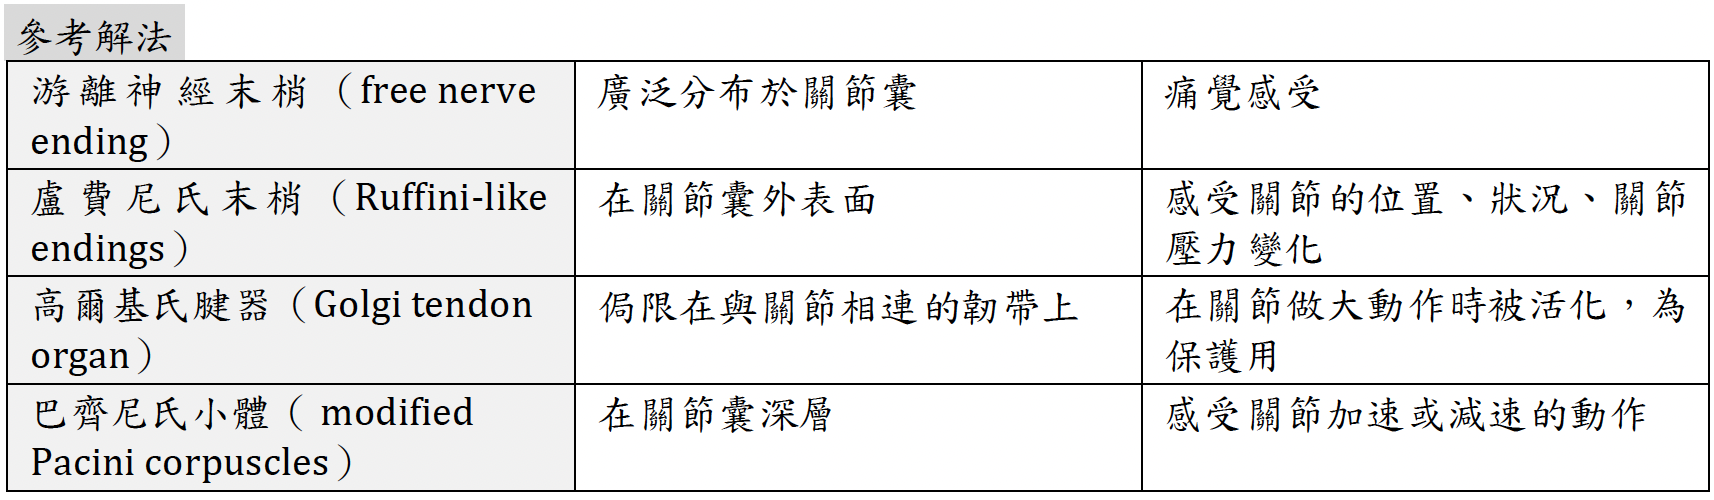

TMJ

Join capsule

Ligament

- Stylomandibular ligaments

- Sphenomandibular ligaments

Info

Stylomandibular ligament 分隔 parotid ,submandibular g.